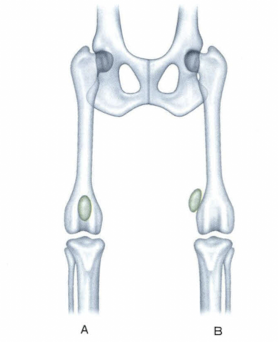

Premium Surgeon 整形外科・神経外科 P56 より

膝蓋骨脱臼とは、膝蓋骨が大腿骨遠位の滑車溝から外れ、内側もしくは外側に変位した状態を言います。現状の状態を指し示している「症状」であって、「病名」として扱わないという認識が正しいのかもしれませんが、実際は病名として扱われていることが多いです。膝蓋骨脱臼の原因は、一般的に先天性(発育性)と外傷性に分類されることが多く、臨床的にはそのほとんどが先天性です。しかし、本当の意味での先天性というものはほとんど存在せず、発育性(進行性)に脱臼が認められます。

先天性(発育性)の膝蓋骨脱臼の根本的な原因ははっきりわかっていないところが多いですが、①大腿四頭筋群の発育障害、②大腿骨や脛骨における骨格的形態の変化、③膝蓋骨の高位などが原因と考えられています。そのため、術式の選択においても、考えられる原因やその変形の程度によって、アプローチすべき問題が変わってくることがあり、術前の触診やレントゲンでの評価が重要になってきます。